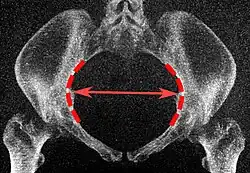

Low-dose 3D-rendered CT scans can be used for estimating the main pelvimetry parameters:[4]

Parameter Maximum intensity projections[5] Thin slices End points Normal measures

Obstetric conjugate

Median plane, 20 mm thick

Same, but may require minor side-to-side scrolling to visualize both end points. The line between the closest bony points of the sacral promontory and the pubic bone next to the symphysis 10 to 12 cm.[4]